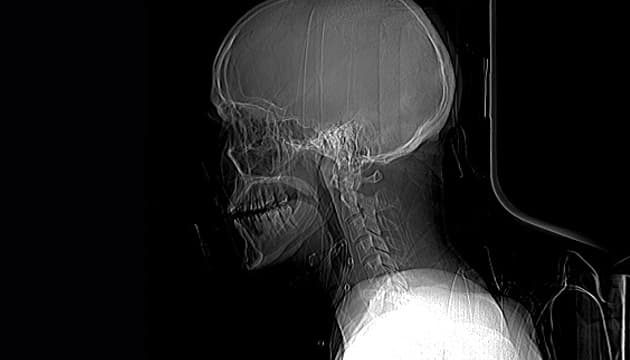

#2 Autopsia virtual

Una forma de lidiar con eso será la autopsia virtual, en la que diferentes dispositivos podrán escanear el cuerpo y crear una proyección tridimensional. Gracias a herramientas informáticas y softwares especiales, los forenses podrán realizar los mismos trabajos que harían sobre el cuerpo real, pero en el duplicado virtual. Por si fuera poco, la digitalización de la información permite compartir los datos al instante con diferentes colegas sin importar las distancias, pudiendo obtener así resultados más completos, gracias a una "segunda opinión".